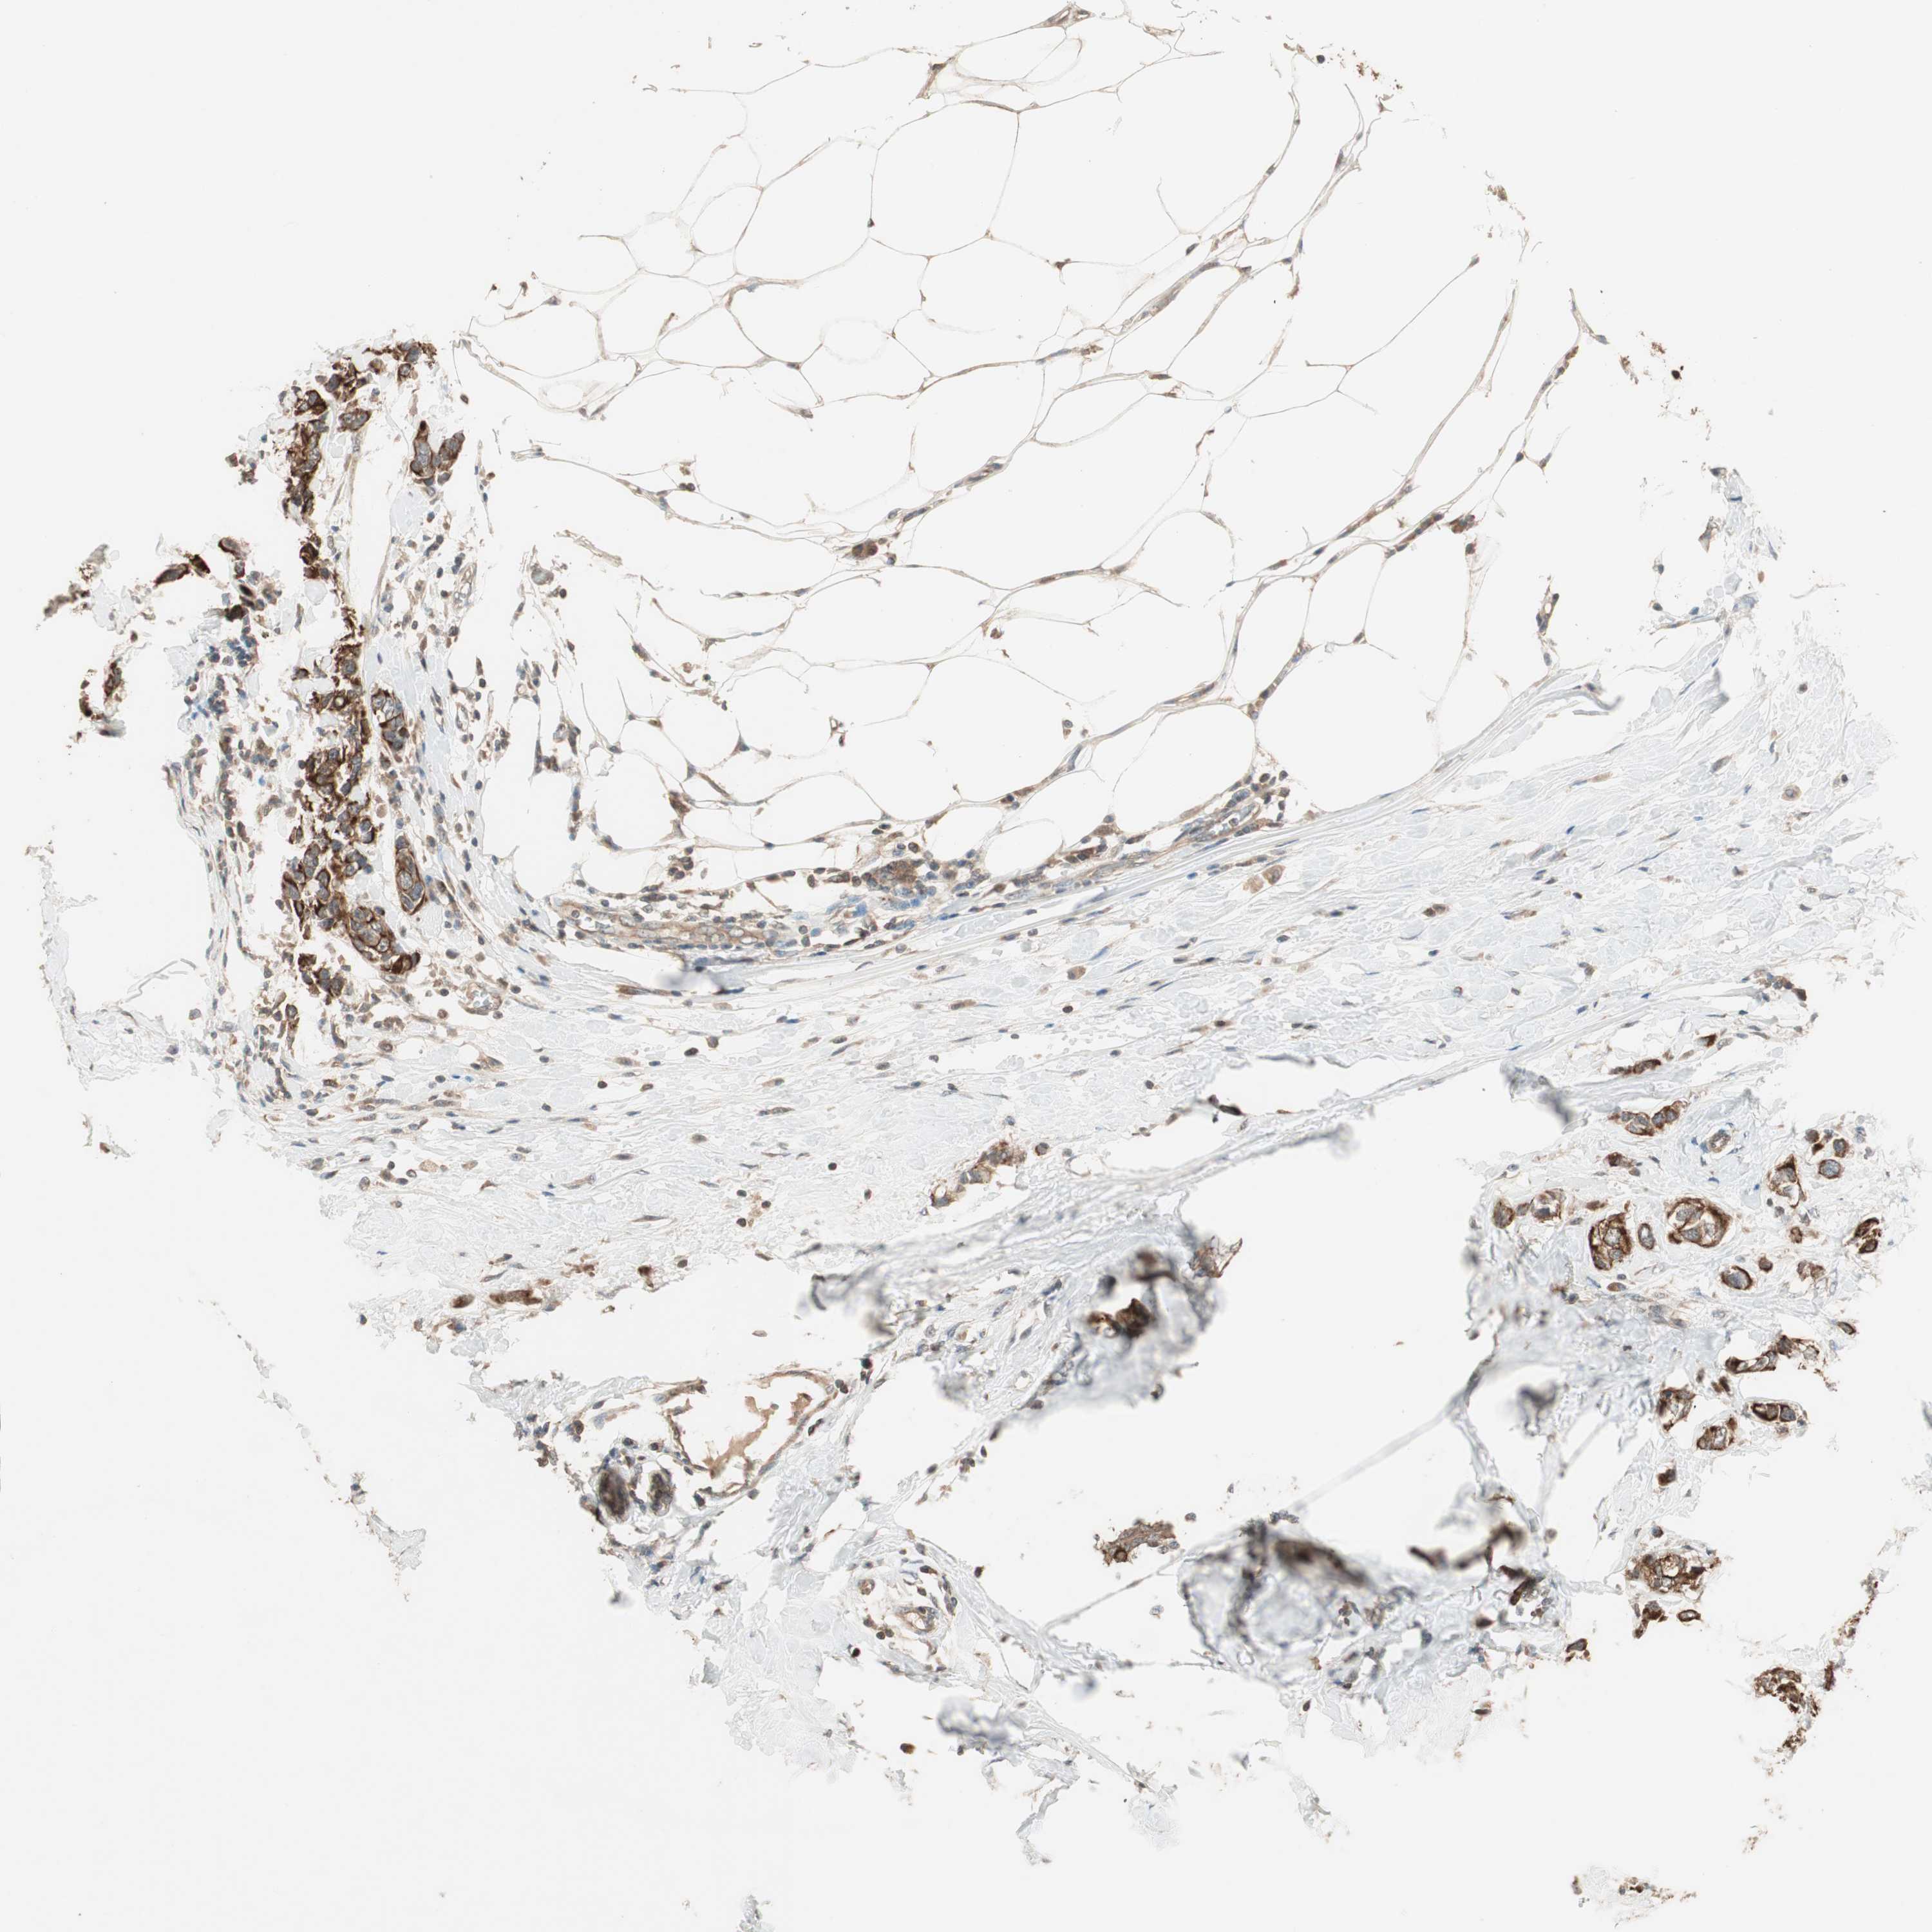

CANCER BREAST CANCER Show tissue menu

BRCA TCGA BRCA VALIDATION PROTEIN EXPRESSION